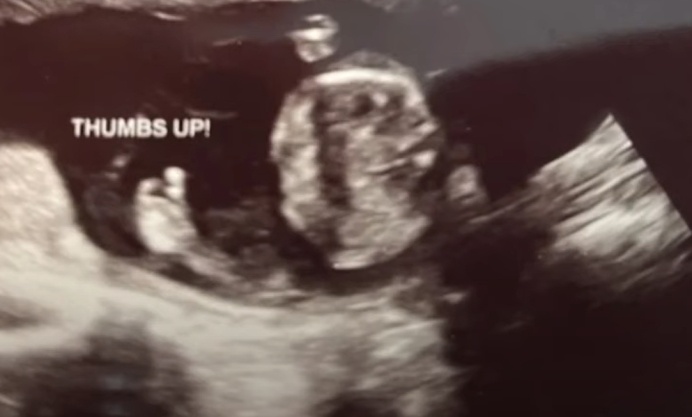

Minionej jesieni do Pregnancy Center East zgłosiła się matka, która chciała zobaczyć swe dziecko na USG. Była ostatnią pacjentką tego dosyć trudnego dnia. Gdy wykonująca badanie Lauren Purtee najechała głowica na dłoń maleństwa, na ekranie pojawił się jego kciuk uniesiony w górę w dobrze znanym, choć oczywiście nieświadomym geście. Wszyscy w pokoju roześmiali się serdecznie.

Ta sytuacja natchnęła obrońców życia z Cincinnati otuchą.